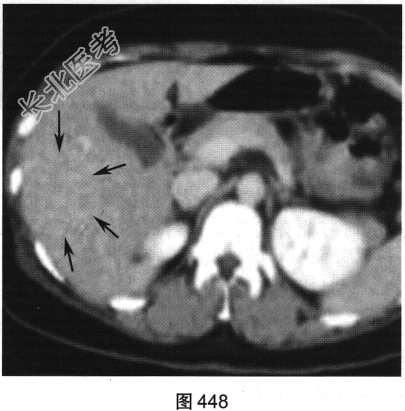

- 多项选择题2.[提示]患者行CT三期增强扫描,如图446~图448所示。对患者CT三期增强扫描图像描述正确的是( )

A、动脉期病灶明显强化

B、门脉期病灶无强化

C、病灶位于肝S5/6,边界清

D、延迟期病灶呈等密度

E、病灶为富血供肿瘤

F、门静脉期病灶为低密度